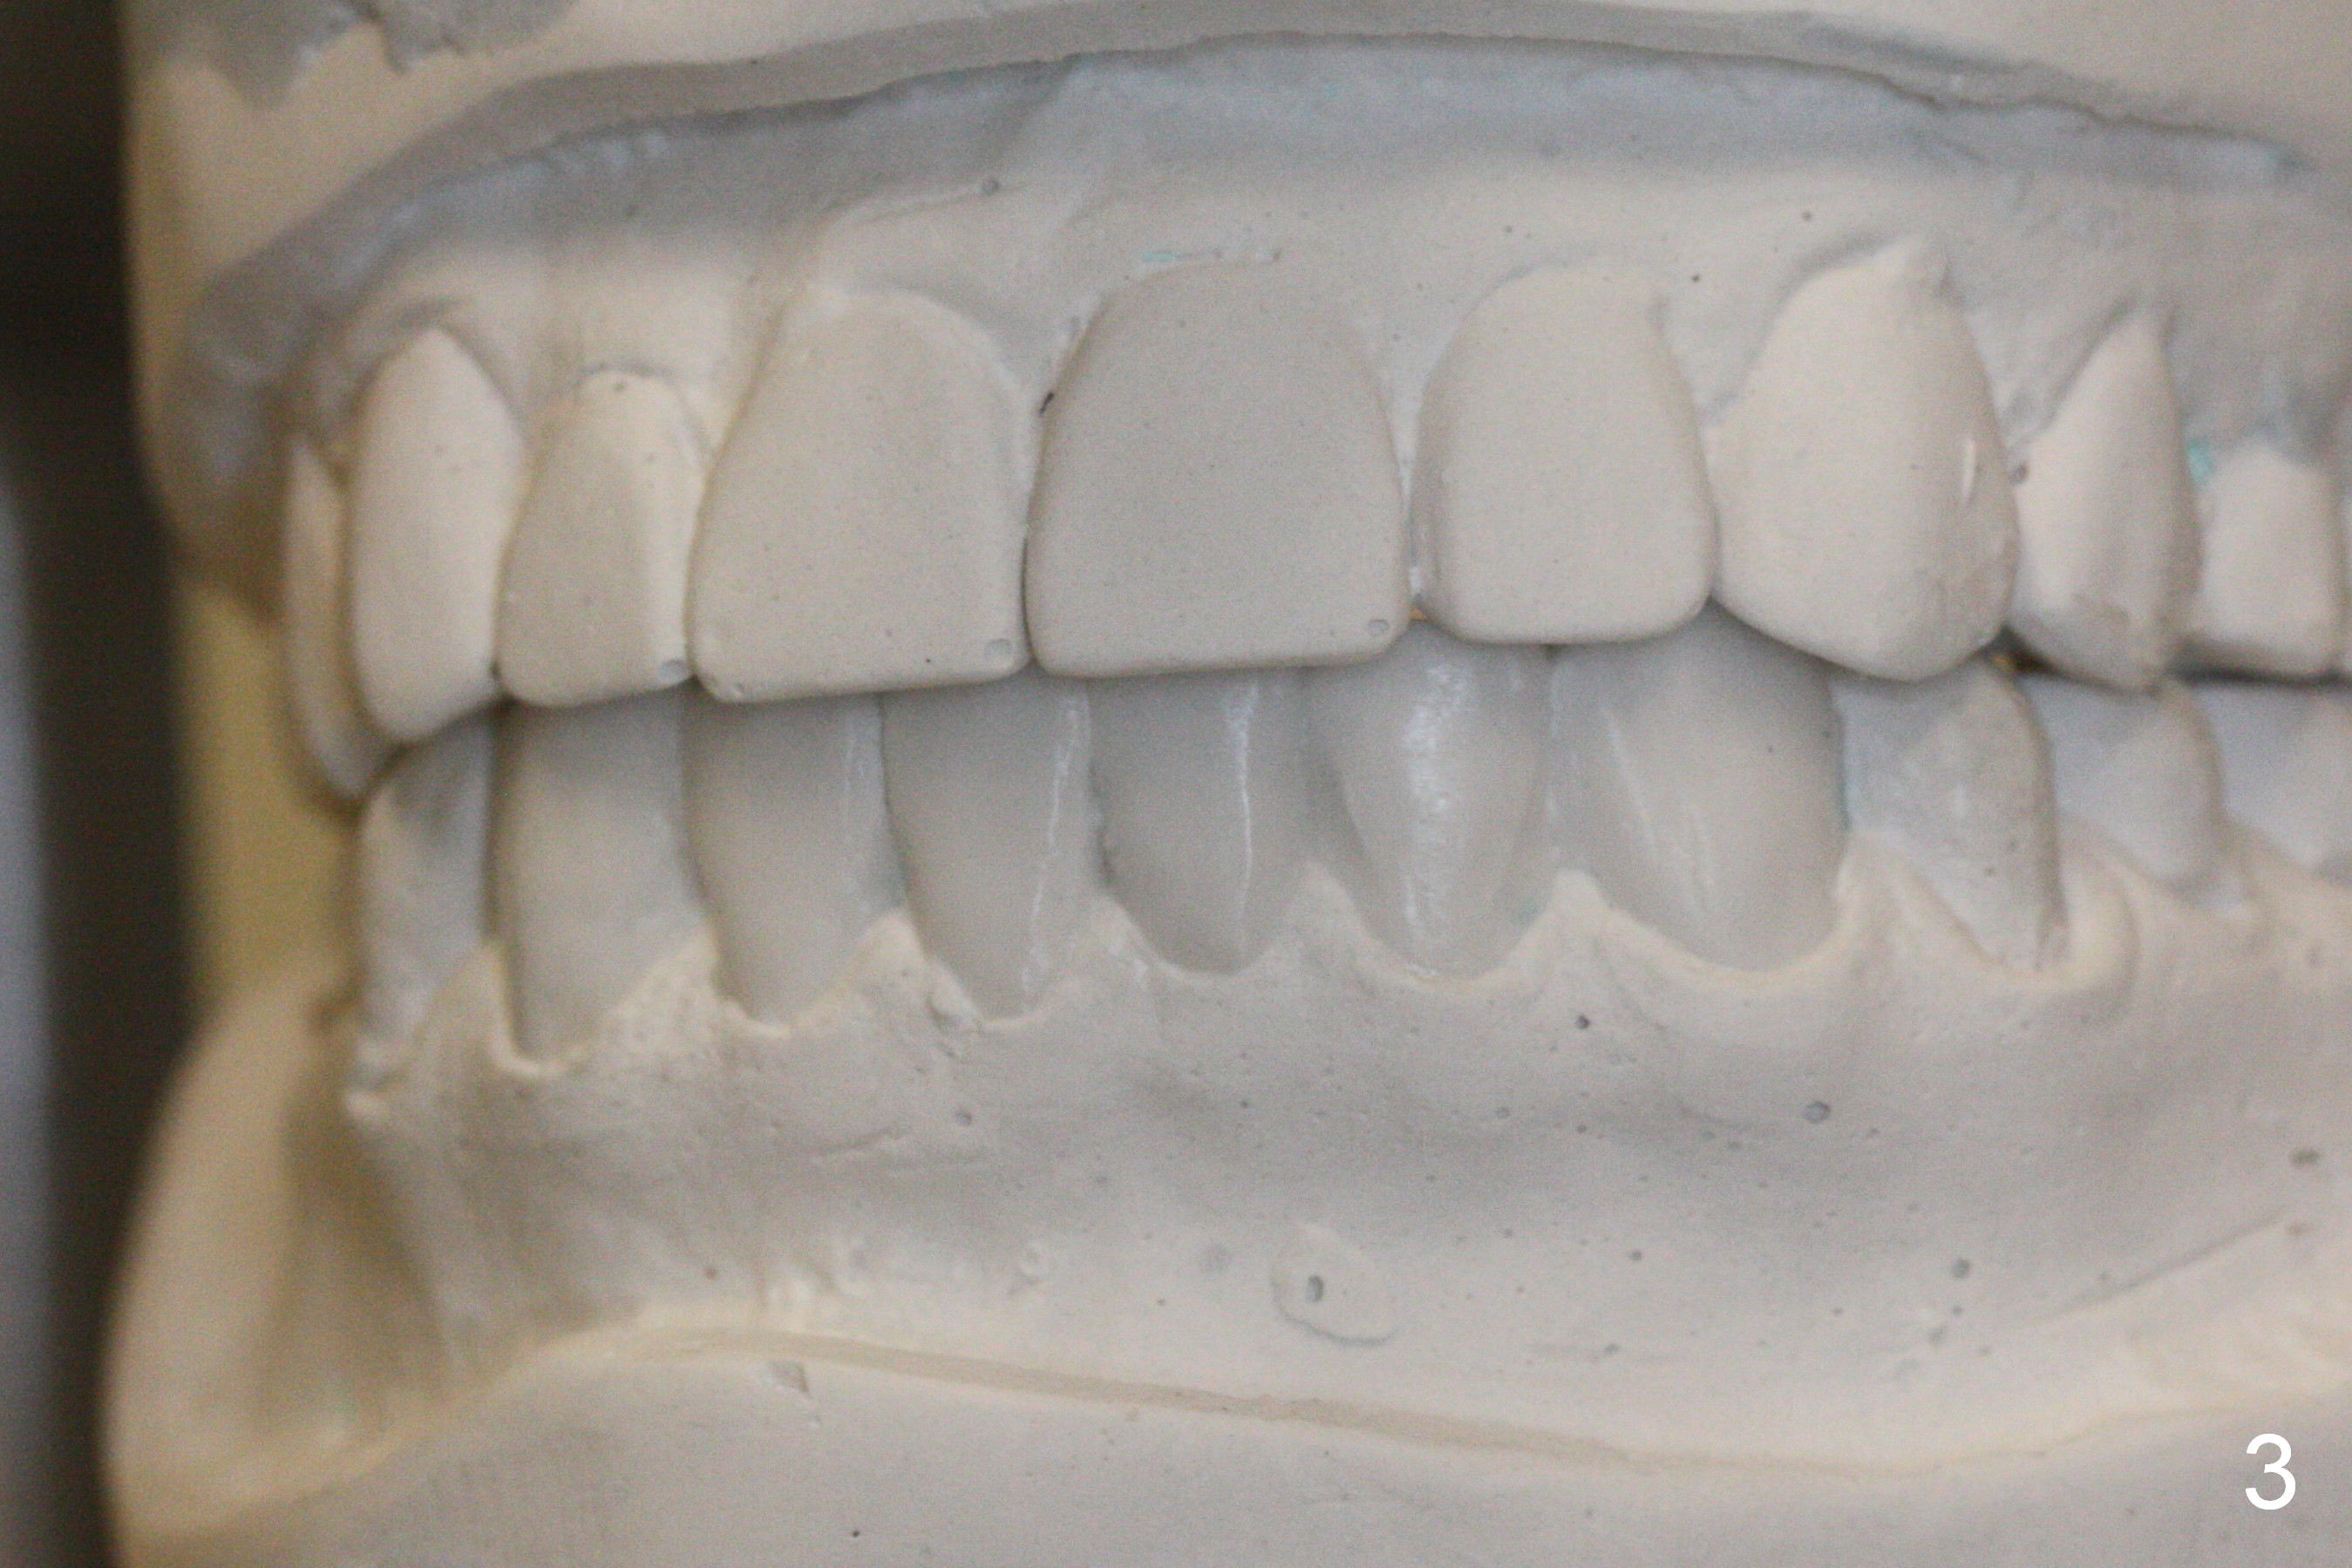

Wax Up for Lower Anterior Veneers

A 46-year-old woman has Tetracycline teeth. She is pleased with upper veneers and wants to do the same for the lower anterior teeth, which are crowding (Fig.1,2). Wax up (Fig.3,4) lays foundation for fabrication of reduction and provisional stents.